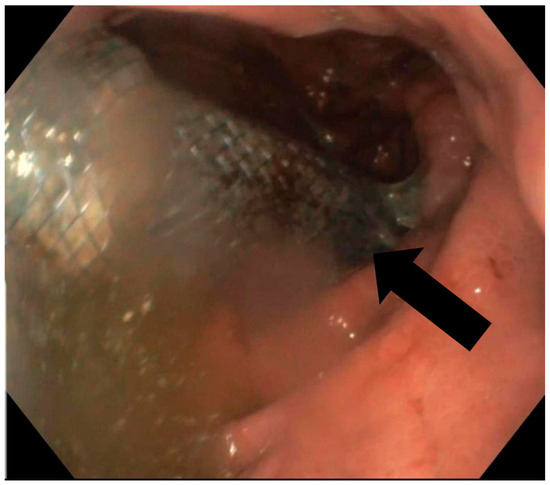

A follow-up endoscopy was routinely performed within 6–8 weeks, provided no adverse events occurred, to remove the stent, assess the treatment’s effectiveness and determine if additional intervention was needed (Figure 3). During this and any subsequent endoscopies, the migration and removability of the stents were evaluated, along with the persistence of the leak following the contrast injection (after the removal of the stent and/or any remaining clips). Endoscopic treatment was repeated until either the treatment was deemed effective, surgical intervention was required or the patient succumbed.

Figure 3. Eso-jejunal anastomosis after stent extraction with closed fistula after the resection of a gastric neoplasm.